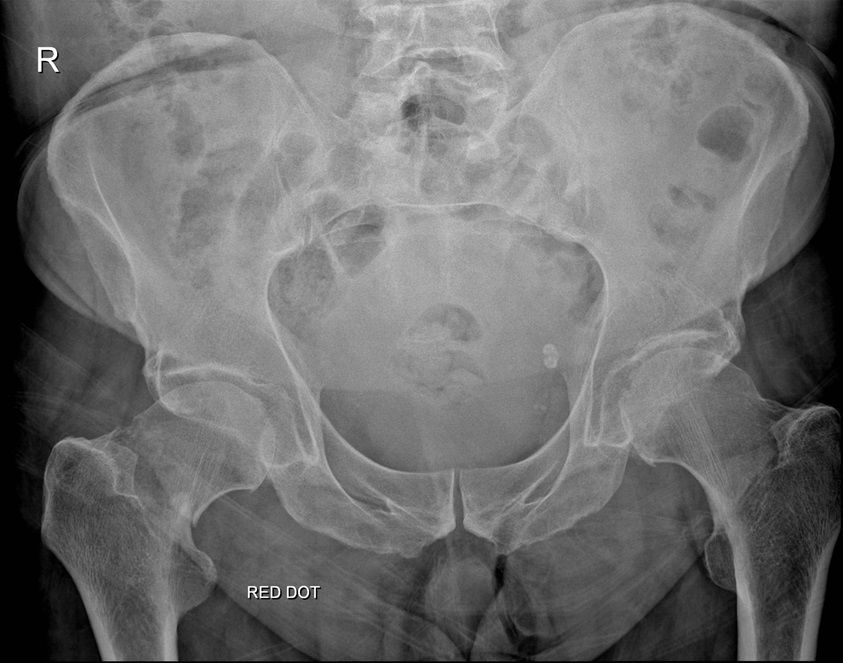

Question 2

Question

Which operation would you perform?

Answer

• THR

• Hemiarthroplasty